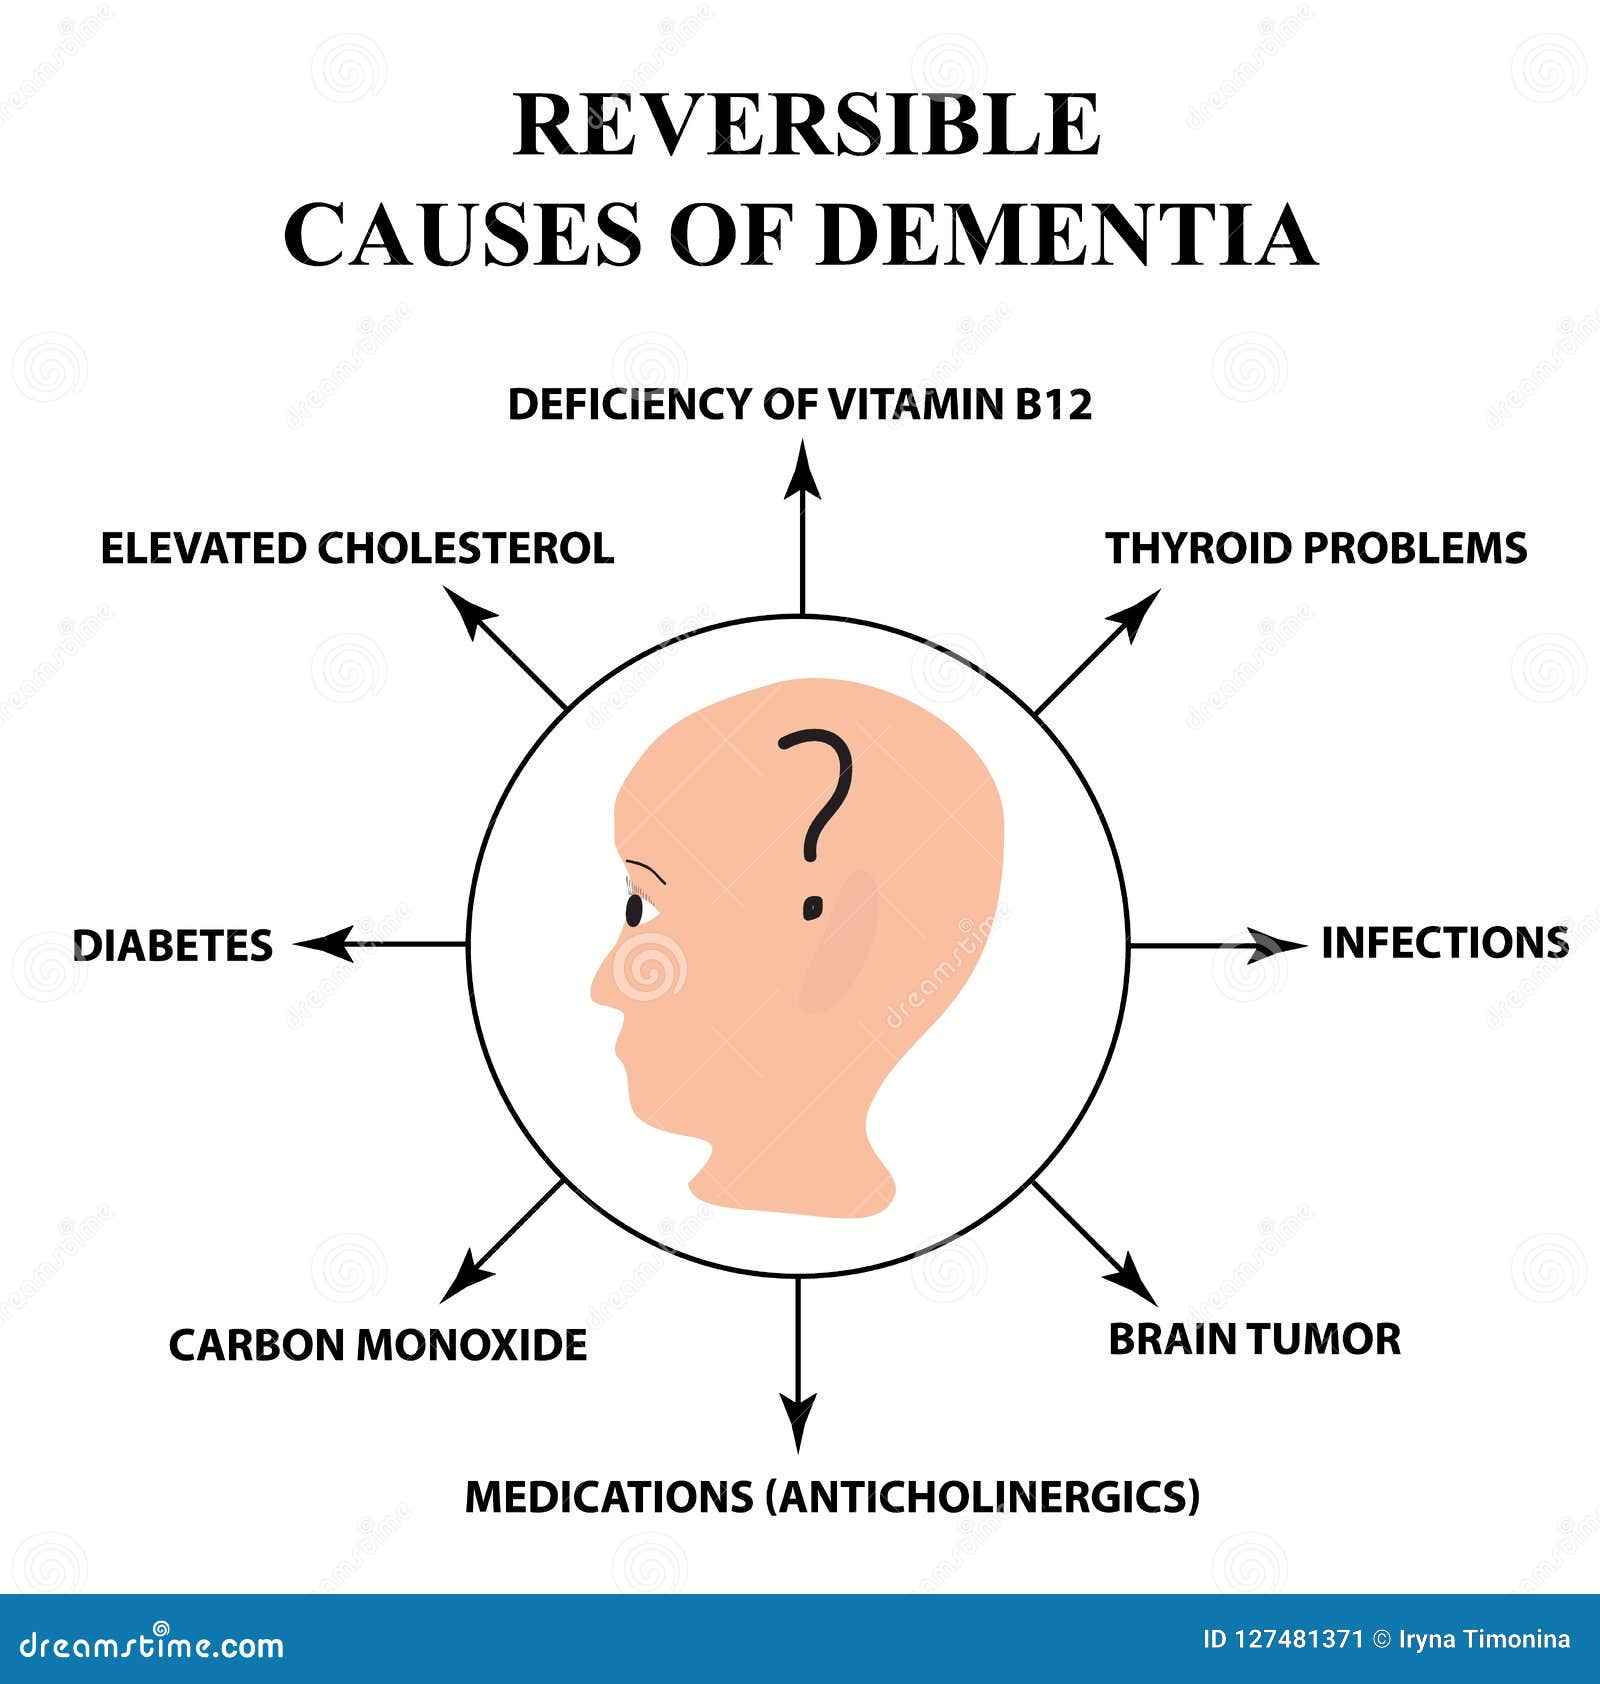

Reversible Causes of Senile Dementia. Alzheimer`s Disease. Infographics …